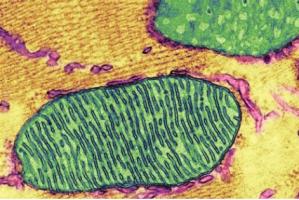

Actualité publiée le 23/02/2017PARKINSON : Cibler les mitochondries pour booster les neurones

PARKINSON : Rétablir les lipides des mitochondries pour bloquer la maladie